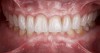

Fig 21. Postoperative frontal intraoral view in maximum intercuspation with full-contour high-translucent zirconia restorations.

Figure 21

A 40-year-old patient presented with the chief complaint: “My teeth are cracking, and I would like to have my original bite.” Dental findings included Class I occlusion with slight misalignment between teeth Nos. 8 and 9. Generalized severe occlusal wear and slight Class I mobility of teeth Nos. 23 to 26 were noted. Caries lesions were found on teeth Nos. 2, 4, 6, 8, 9, and 14 and abfraction lesions on teeth Nos. 4, 5, 10, 11, 13, 20, and 21. Figure 1 through Figure 3 depict the preoperative situation. Full-mouth rehabilitation was suggested. The goals for the restorative treatment were management of erosive etiology, conservation of tooth structure, and long-term protection of the restorations. A diagnostic wax-up was instrumental in determining functional and esthetic treatment goals and establishing new anterior guidance (Figure 4). A comprehensive, step-by-step treatment approach was applied, which, after periodontal pretreatment, caries control, and provisionalization, included definitive preparation (Figure 5) and restoration of the maxillary anterior teeth to establish anterior occlusal guidance. CAD/CAM–fabricated full-contour monolithic high-translucent zirconia crowns (Katana™ UTML Ultra Translucent Multi-Layered, Kuraray Noritake Dental, kuraraynoritake.com) were fabricated (Figure 6 and Figure 7) and cemented with self-adhesive resin cement (Panavia SA, Kuraray Noritake Dental). Figure 8 demonstrates the cemented anterior crowns and refined conservative preparations of posterior teeth, which were performed with minimal tooth-structure removal. High-translucent monolithic zirconia onlays and crowns were fabricated (Katana Zirconia UT, Kuraray Noritake Dental) (Figure 9 to Figure 12). The posterior restorations were adhesively bonded following the APC zirconia-bonding concept. APC-Step A involved air-particle abrasion with 50-μm aluminum oxide at 1.5 bar with a chairside microetcher (Figure 13), followed by application (APC-Step P, Figure 14) of a special ceramic primer (ClearfilTM Ceramic Primer, Kuraray Noritake) with adhesive phosophate monomers (MDP). Relative moisture and contamination control was achieved with cotton rolls and retraction cords. Rubber dam placement, which is always preferred, was difficult in this situation. The enamel surfaces of the abutment teeth were selectively etched (Figure 15) with 35% phosphoric acid (K-Etchant Gel, Kuraray Noritake Dental) and the dentin conditioned (Figure 16) with a self-etch dentin primer (Panavia V5 Tooth Primer, Kuraray Noritake Dental). A dual-cure adhesive resin (Panavia V5 Paste Universal, Kuraray Noritake Dental) was dispensed directly into the restorations with an automix syringe. The restorations were inserted, and excess cement was carefully removed (Figure 17 and Figure 18) before light polymerization (Figure 19). Postoperative views depict the treatment outcome (Figure 20 to Figure 22).